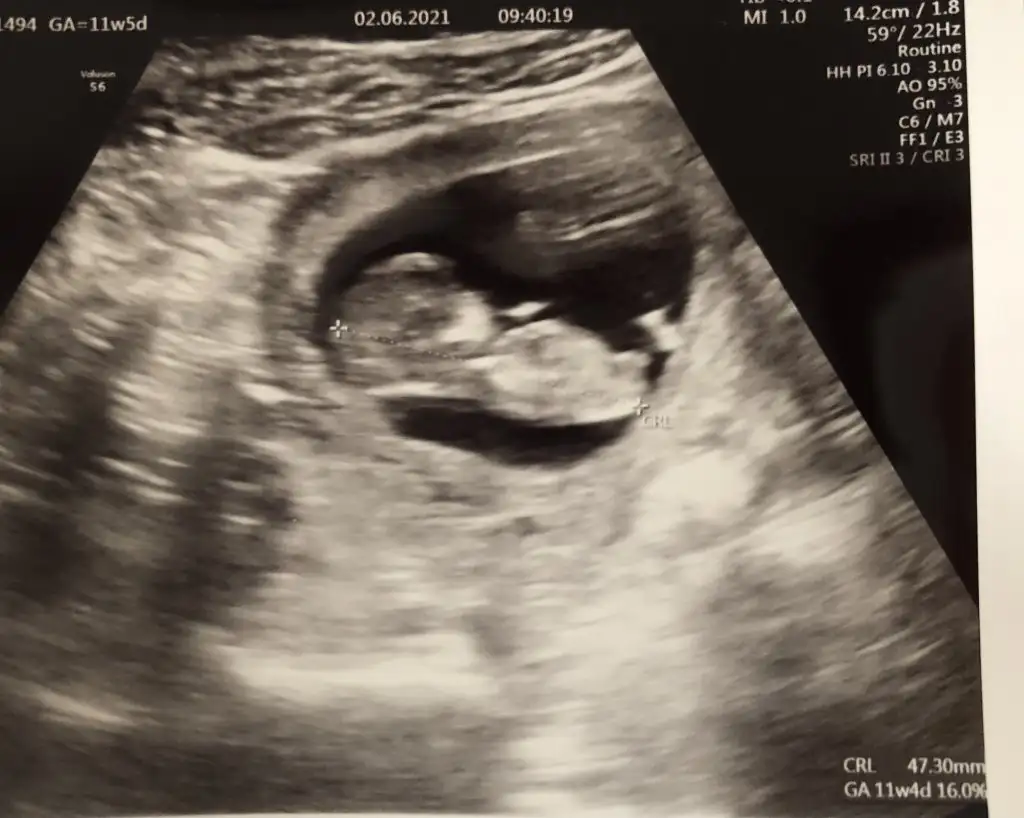

Kızlar benimkine de bi bakabilir misiniz

Ikra meyra Ikra meyra canim gecen sene kizimi tahminde dogru bilmistin 13+3haftalik tekrar gebeyim bi tahminde bulunurmusun bugun gittim devlette 16.haftaya kadar yasal olmadigi icin demiyorlarya dr al sen bak dedi verdi güldu🙃

Yaaa maşallah 🧿 kız gibi sanki emin olamadım